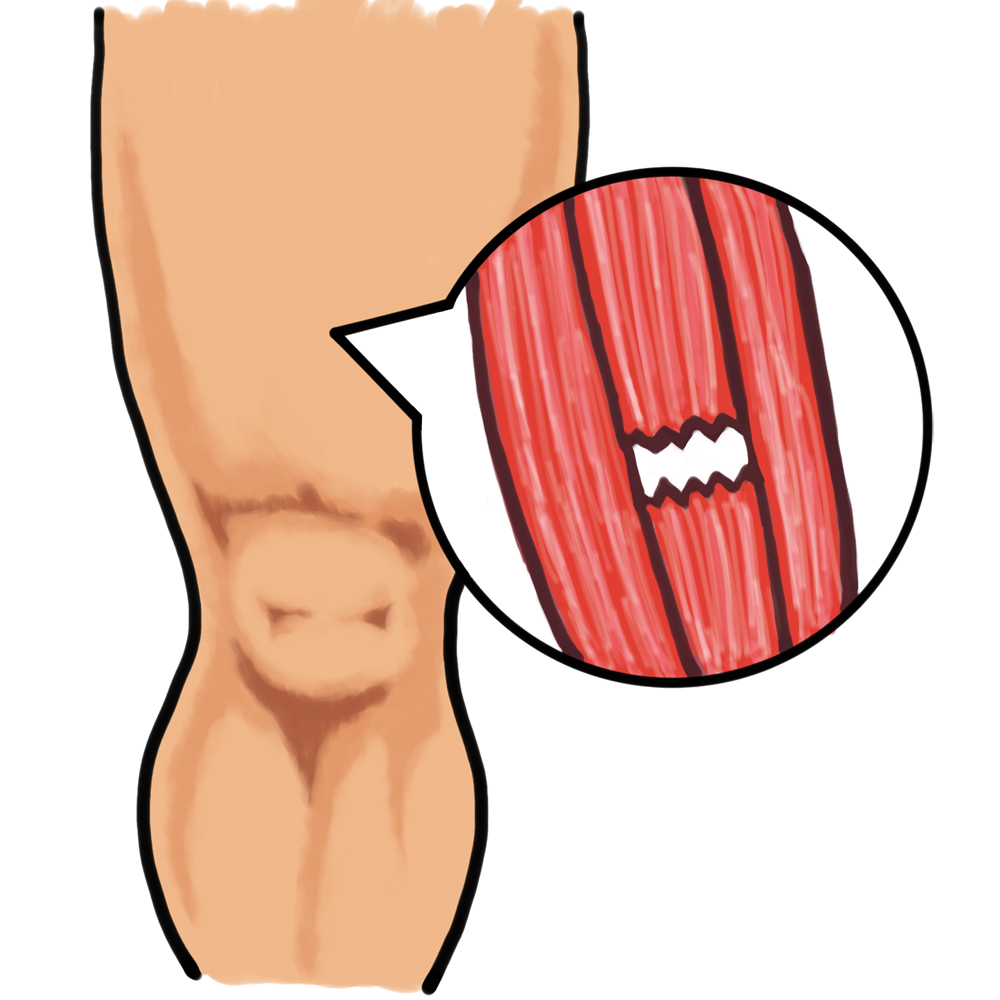

肉離れとは、スポーツ活動中などの急激な筋肉の収縮により、筋線維や筋膜などを損傷し、スポーツ活動を続けることができなくなった状態である。

名前を見ると筋肉が離れていく様に思われるが、実際は筋肉が腱から離れていく状態をいう。

筋肉の部分断裂のみではなく完全断裂も含んでいる。